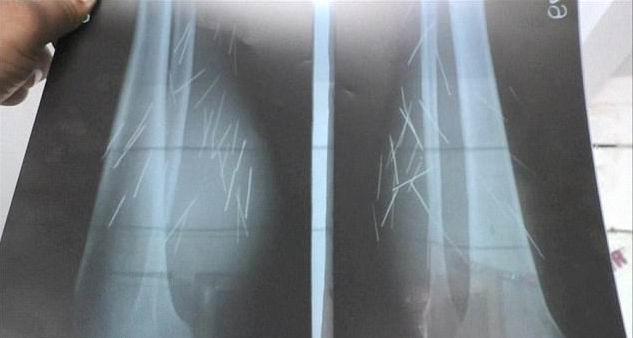

Наконец, 25 октября 2017-го женщину госпитализировали. Она оказалась в районной больнице в Фатехпуре (Fatehpur), где врачи были шокированы, просматривая ее рентгеновские снимки.

'Мы сделали несколько рентгеновских снимков всего ее тела, после чего обнаружили 70 различных железных игл в ее ногах, в области ниже колен'.

'Полное сканирование помогло определить, что в других участках тела гвоздей нет. Иглы были только в ногах, больше нигде'.

Вишал добавляет: 'За всю свою медицинскую карьеру я не сталкивался с такими делами. Мы обнаружили так много игл в ногах Анасуйи, что просто не понимаем, как она могла так долго терпеть боль. Ее страдания просто огромны'.